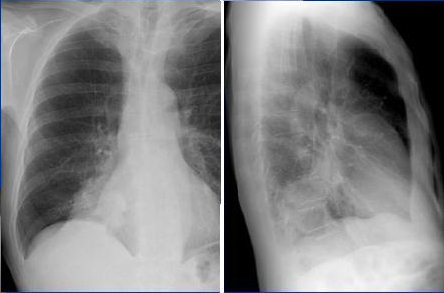

Image radiologique normale du

thorax ( radioanatomie du thorax )

Imagerie du thorax se base sur les techniques

radiologiques : La radiographie standard , la

tomodensitometrie , l'imagerie par resonance magnetique (

IRM ),l'echographie scintigraphie

ventilation-perfusion , arteriographie bronchiques , la

bronchographie seraient donc capital d'adapter a demande sur

la situation clinique et d'informer clairement du medecin

speciale .

La bien interprete des images radiologie - pathologiques

pulmonaires se base sur la connaissance suffisament des

images radiologiques normales du thorax.

Image radiologie normale de la

paroi thoracique (Radioanatomie )

- La Radiographie standard ( cliche de

face et de profile ).